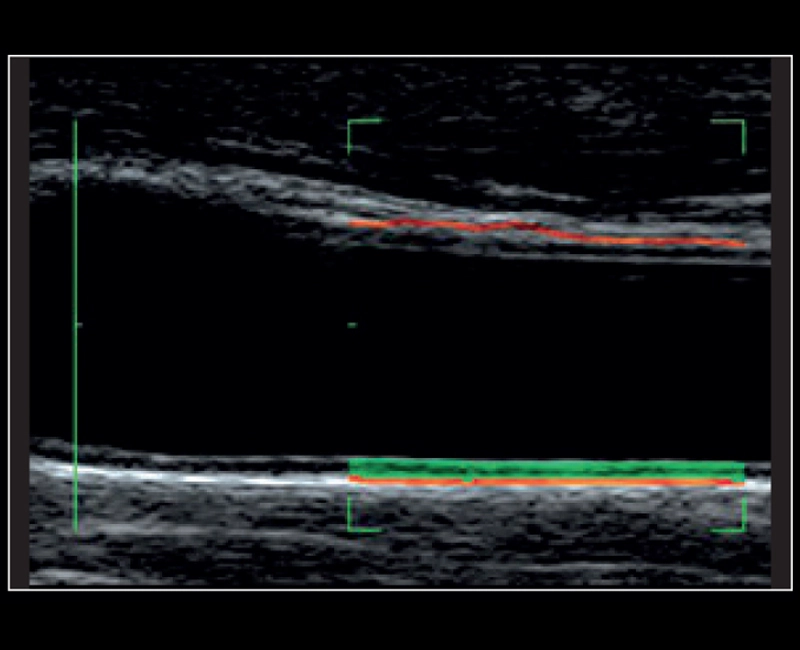

MyLab™9 Platform - QIMT Intima-media thickness quantification based on radio frequencies in real-time studies

MyLab™9 Platform - QIMT Intima-media thickness quantification based on radio frequencies in real-time studies